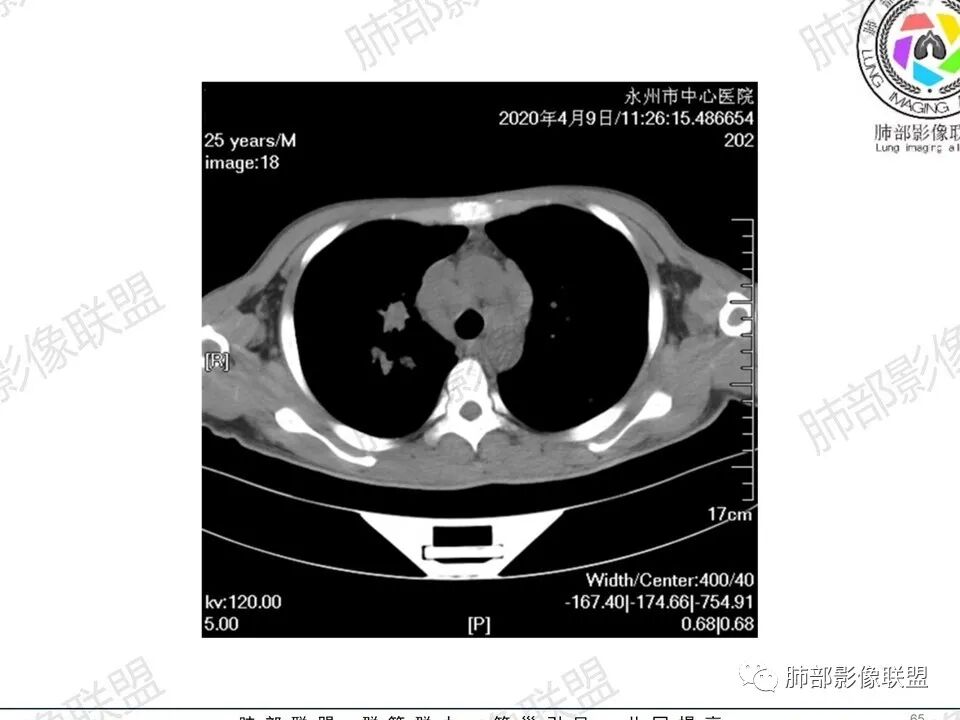

3、影像表现:双肺散在斑片影及结节影,部分结节内可见血管穿行,斑片影沿支气管血管束分布,近胸膜侧病变收缩不明显。部分中央淋巴间质增厚,小叶间隔增厚。病灶内支气管穿行,部分支气管略扩张。局部小结节呈串珠样改变。纵隔、肺门区、锁骨上及腋窝淋淋巴结肿大,部分有融合。心腔低密度。脾大。

5.双肺门及纵隔淋巴结显著增大,这改变相当显眼。这里强调“双肺门”及“多发”!

增大的淋巴结密度偏低且均匀。此外患者有体表淋巴结增大。

1.临床表现明显,纵隔及双肺门淋巴结显著肿大,临床最为担心的还是淋巴瘤!

尤其患者有贫血及脾脏增大,又有体表淋巴结增大时,这也是临床相对常见的情形。

淋巴瘤肺部浸润表现多样,多发结节影是其最常出现的影像学改变,尤其是霍奇金病。

2.右肺多发微小结节影,部分沿血管束分布,尽管未见小叶间隔改变,但双肺门淋巴结增大确实应当首先排除结节病,但经验上说,结节病的增大淋巴结密度往往较高、较密实,边界往往清楚,“独立性”很强,绝无“融合之嫌”!此外,较少出现贫血、脾大,临床表现也往往较轻微。